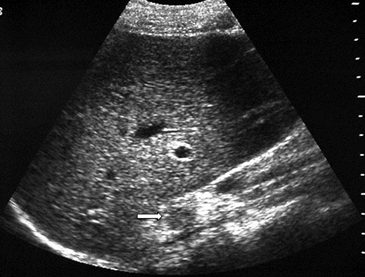

Las masas suprarrenales son un hallazgo frecuente en la población general, con una prevalencia que varía entre un 1a un 8,7% en grandes series de autopsias. Los incidentalomas se describen en aproximadamente un 4-6% de la población (Figura 4 a y b), y su prevalencia aumenta con la edad, siendo de 0,2% en pacientes entre 20 a 29 años, y de 7 a 10% en pacientes de mayor edad4. Se observan también con mayor frecuencia en pacientes obesos y diabéticos, especialmente de sexo femenino.

A

BLa mayoría de estas lesiones, hasta un 98% de los casos, resultan benignas en el contexto de pacientes sin historia conocida de neoplasia maligna. De modo contrario, si existe el antecedente de una neoplasia maligna extraadrenal la probabilidad de que un incidentaloma suprarrenal corresponda a una localización secundaria aumenta significativamente. Hasta un 27% de los pacientes oncológicos tienen metástasis suprarrenales microscópicas y aproximadamente un 50% de las lesiones suprarrenales pesquisadas de manera incidental en este tipo de pacientes representan enfermedad metastásica4.